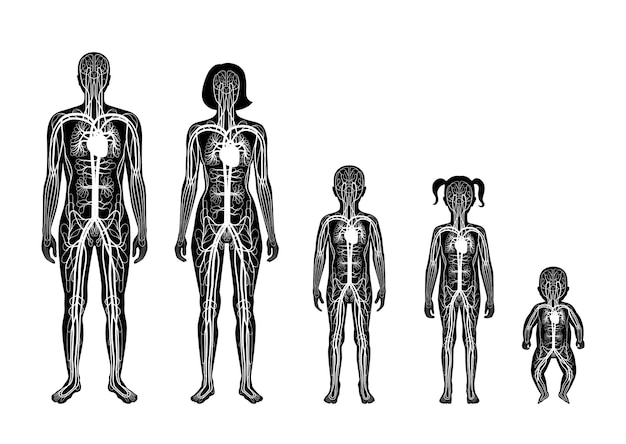

Human Arterial And Venous Circulatory System Anato 21139490

14/11/2025

ร่างกายมนุษย์